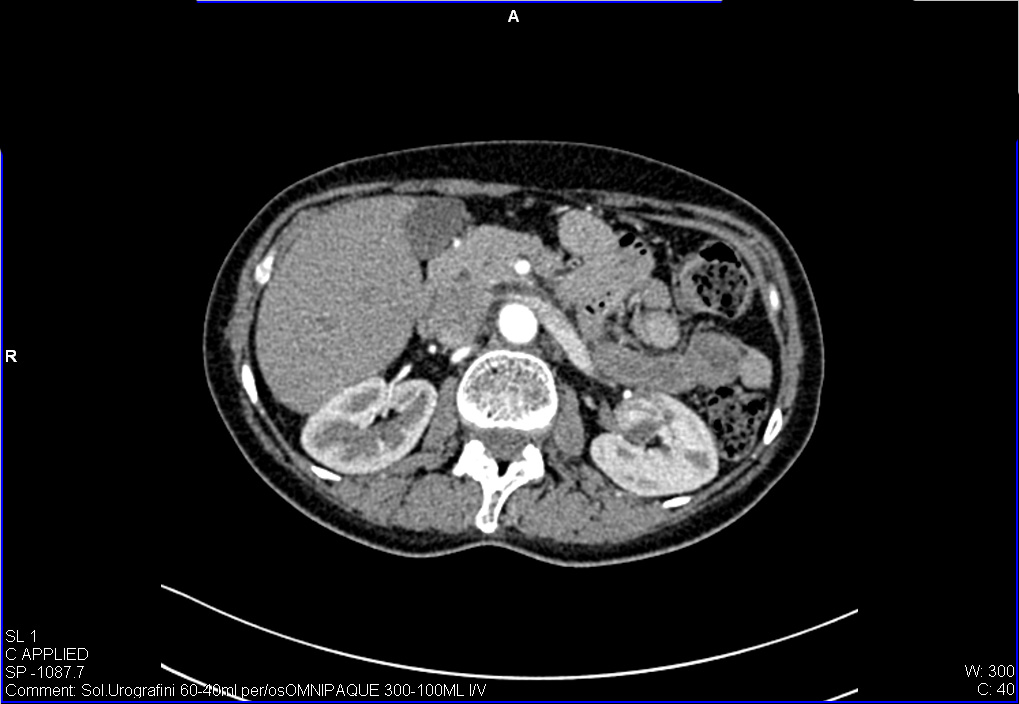

Женщина средних лет, жалоб нет.

УЗИ почек - малый рак. Small RCC.

Позвонили пациентке, она сделала КТ - новообразование подтверждено.